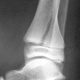

Через 1,5 месяца после наложения гипса.

Гипс надо снять. От физкультуры освободить на 1,5 месяца.